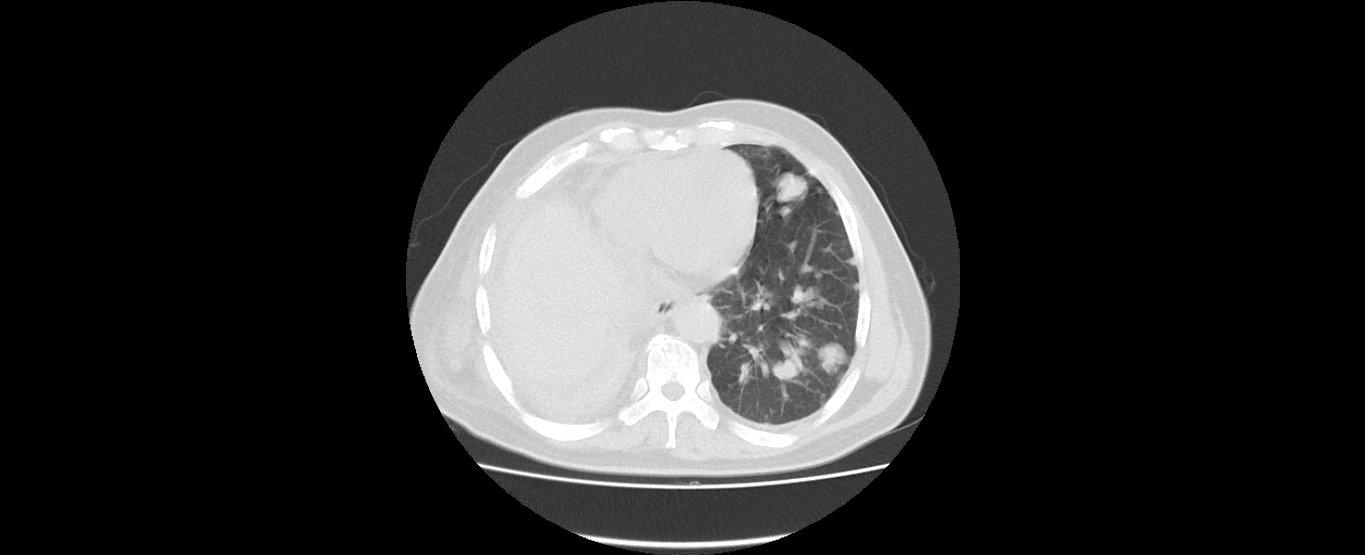

患者刘某某,男,60岁,因“右下肺中央型肺癌”2008年6月在外院行“右下肺癌根治术+右上肺部分切除术”,术后行化疗和放疗。2011年4月复查CT提示肿瘤复发,行化疗及靶向药物治疗,肿瘤控制;2016年8月新发肺转移,再次行化疗及靶向治疗,辅助中医药治疗,2017年2月复查,病情平稳。目前患者生活质量较好,没有不适症状,按时返院复查。

2017年2月